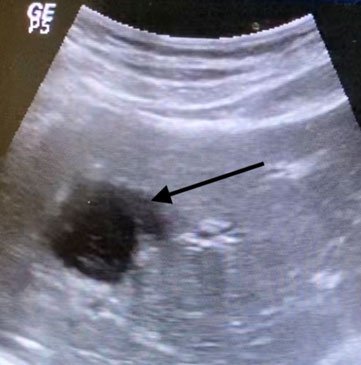

Before procedure liver abcess (arrow)

After procedure (PCD): shrunken liver abcess (black arrow) and drain (white arrow)